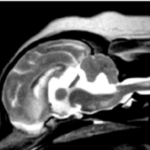

T1強調画像(造影)

FLAIR画像

Saggital画像

Coronal画像

画像は9歳のゴールデンレトリーバーの頭部MRIです。本症例は発作を主訴に来院されました。

MRI検査の結果、前頭葉に脳腫瘍が確認されました。